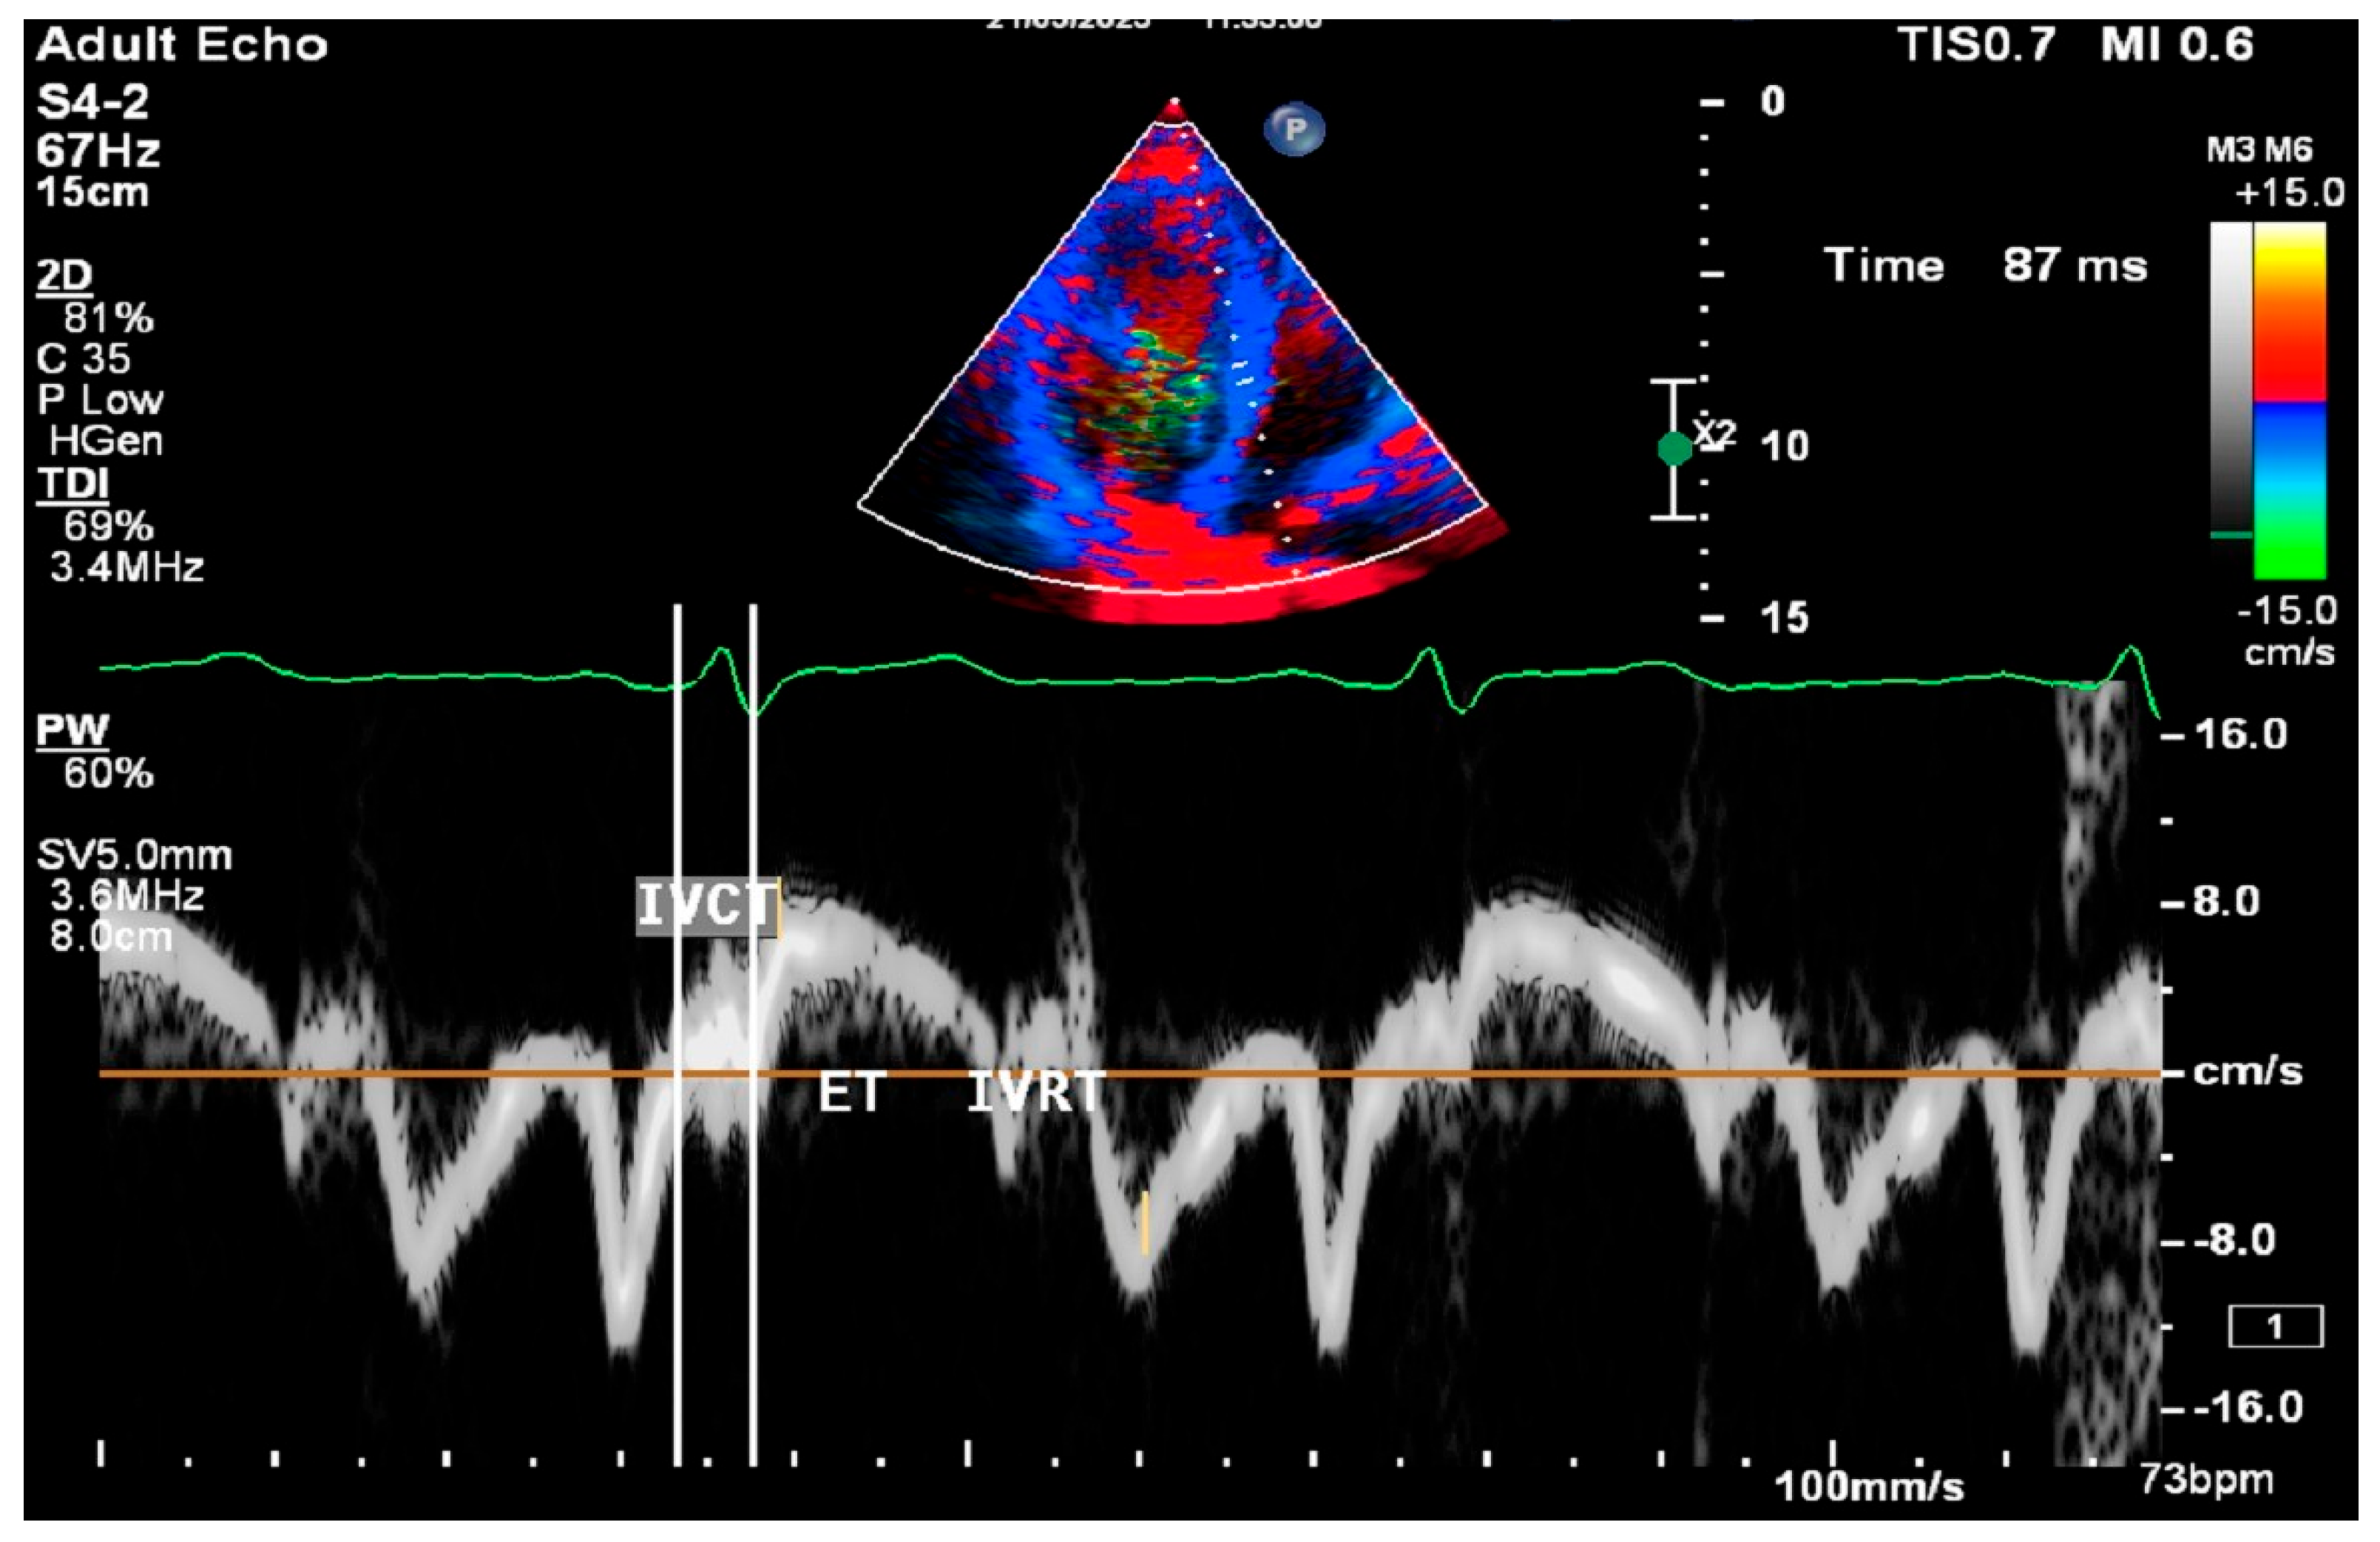

2.8. Cardiac Ultrasound Examinations

2.9. Statistical Analysis